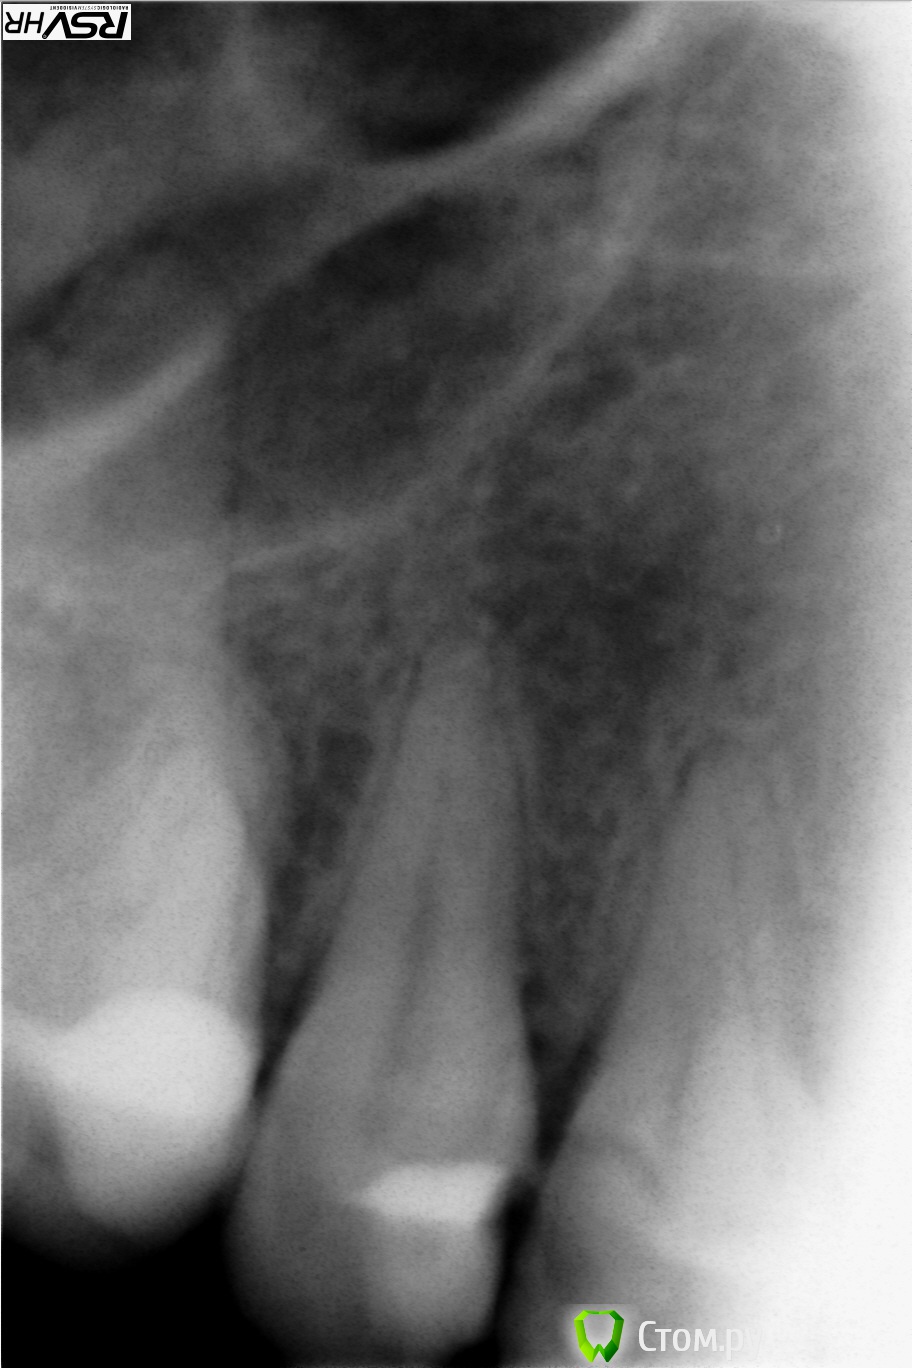

marygan Опубликовано 17 марта, 2014 Поделиться Опубликовано 17 марта, 2014 Добрый день. Первый раз столкнулась с такой проблемой с зубами, очень переживаю и прошу посоветовать. Год назад начал болеть запломбированный зуб (четверка сверху ). Немного шатался и была красная десна, крошилась пломба. Сделали снимок. Доктор в городской поликлиннике ничего объяснять не стала, смутно только сказала, что нужно класть лекарство, а потом пломбу (видимо, имелось в виду удаление нерва). Из-за переезда в другой город делать этого не стала.На этот Новый год пломба раскрошилась и выпала. Зуб перестал беспокоить совершенно. Я все равно обратилась в другую городскую поликлиннику по новому месту жительства. Подчистили кариес (теперь зуб просверлен у обоих корней), поставили временную пломбу.Врач сказала идти и ставить платно коронку в другом месте, так как городские поликлинники этого не делают. Если ставить пломбу - есть риск раскола.Ходила на две консультации. Называют разные цены и четко не говорят, что делать.Подскажите, пожалуйста, самый правильный вариант лечения. Есть шансы обойтись без протезирования?В средствах ограничена, но если что-то необходимо, готова на расходы. Больше всего пугает удаление нерва (зачем, если зуб не болит), сточка зуба (зачем уродовать внешне нормальный зуб) и выкинуть немалые для меня деньги на ветер.Снимок прилагаю, хотя мне кажется его сделали очень плохо и со второго раза. Лично я ничего на нем не вижу Ссылка на комментарий

Гарриевич Опубликовано 19 марта, 2014 Поделиться Опубликовано 19 марта, 2014 С точки зрения обыкновенного человека - зуб выглядит прекрасно и не болит. По этому вопросу мне и нужна консультация. Как раз к адекватному и необходимому лечению я готова и всячески приветствую. Если зуб болел, а потом перестал, это значит, что нерв в нем находящийся либо почил, либо в процессе умирания. Такой зуб нужно вылечить изнутри (запломбировать корневые каналы) и желательно покрыть коронкой, потому, что зуб без нерва становится хрупким и может поломаться и его придется удалить. На счет лечения рекомендовал бы Вам обратится в не государственную стоматологию, к доктору с рекомендациями от "сарафанного радио". Ну и всегда можете обращаться к нам, врачам форума стом.ру Ссылка на комментарий